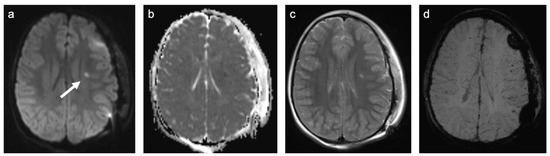

There were only two patients in Group 3. One patient had a history of traumatic brain injury at the age of 1.5 years, the other patient was admitted after a traumatic car accident. A representative case is shown in Figure 5. Both patients were female. They were 7 and 14.5 years old. One patient was examined with contrast-enhanced MRI. None of the examinations showed enhancing lesions. WMSAs in this group of patients were localized supratentorial only. Both patients had multifocal WMSAs.

Figure 5. Representative case “Traumatic white matter injuries”: diffuse axonal injury. DWI/ADC (a,b), T2W (c), and Susceptibility weighted imaging (SWI; (d)) sequences. Fourteen-year-old girl admitted after a traumatic car accident during which she was ejected from her seat. MRI shows a diffusion restricted, diffuse axonal injury lesion in the lobar white matter ((ac), white arrow). SWI demonstrates small regions of susceptibility artefacts at the grey–white matter junction corresponding to cerebral microbleeds (d). Additional findings are a subgaleal fluid collection (left side) following craniotomy for treatment of cranial impression fracture.